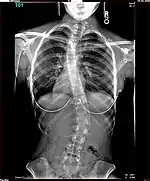

Lateral curvature of the spine in a scoliosis patient

The Harrington Rod, or Harrington implant, is a device for the straightening of the spine inside the body, designed by Paul Harrington. The device consists of a stainless steel rod, attached to the spine at the top and bottom of the curve with hooks. Attached ratchets are then tightened to distract or straighten the spine. Following surgery to insert the rod, the patient wears a postoperative plaster cast or brace for a few months, until vertebral fusion has occurred, after which the cast or brace is removed.[5]